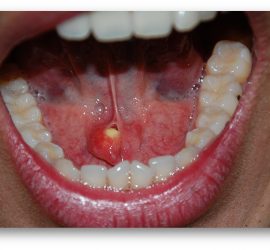

Аденокарцинома — злокачественные эпителиальные опухоли, образующие железистые и папиллярные структуры, но не имеющие характерных признаков других видов рака слюнных желез. Возникают как в больших, так и в малых слюнных железах. Гистологически связаны с протоками слюнных желез. Наиболее характерные морфологические признаки аденокарциномы слюнных желез — пролиферация эпителия в протоковых образованиях в виде […]